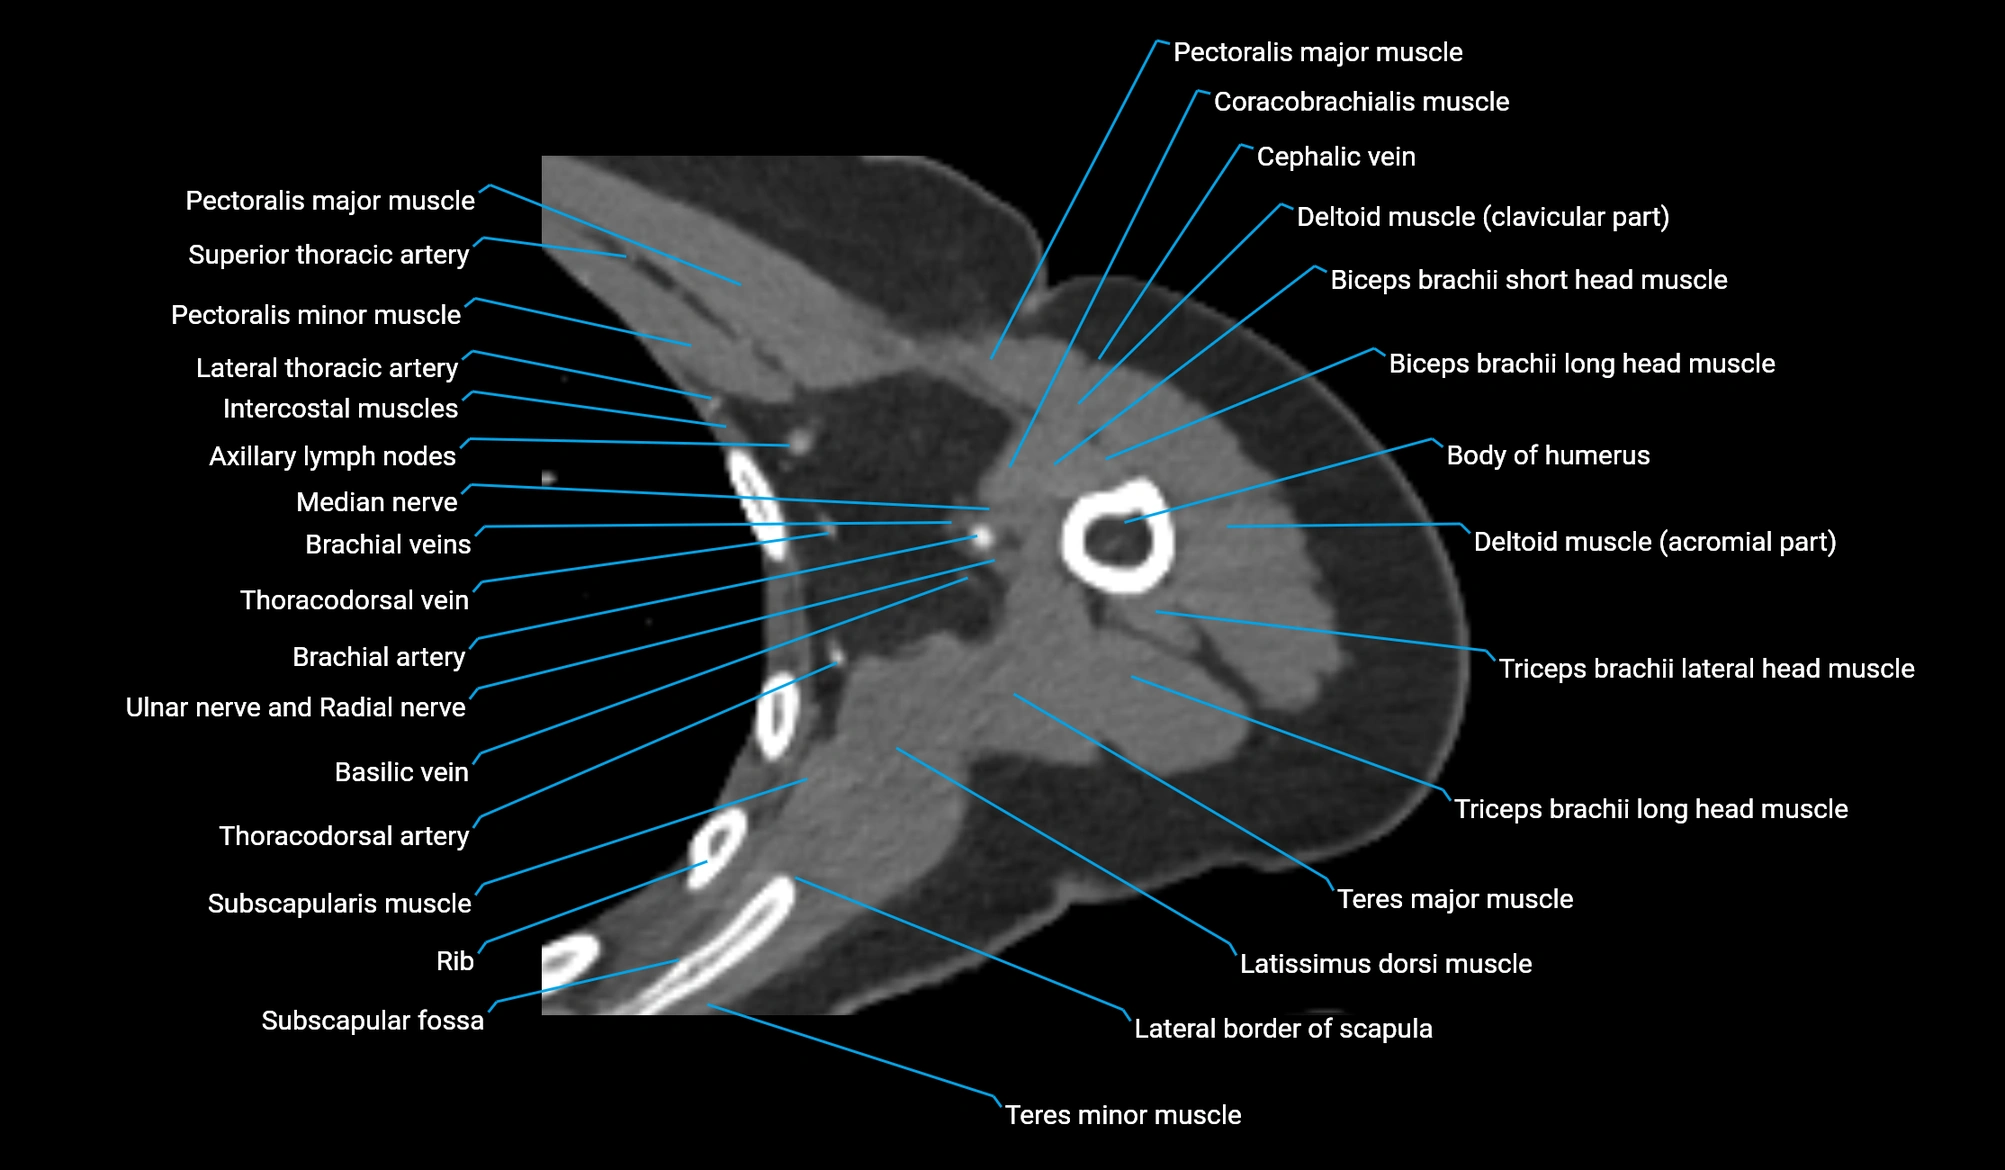

CT image